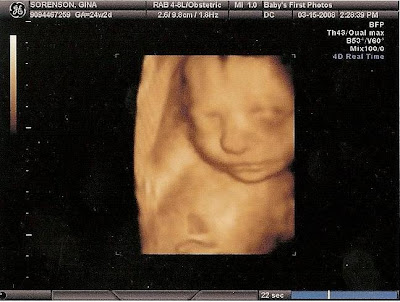

3D ultrasound today =]

When i was pregnant with Aiden i was referred to a place that does 3d ultrasounds. Baby's First Photos did an amazing job with Aidens 3d ultrasound I'm going back today for the 2nd munchkin! I also got a DVD of the ultrasound and pictures =]. Here is one of Aidens. I got this done when i was only 24 weeks along with him. He had no fat on his bones!!! This time i am almost 30 weeks so I'm expecting to see a little chunkier baby this second time around. =]